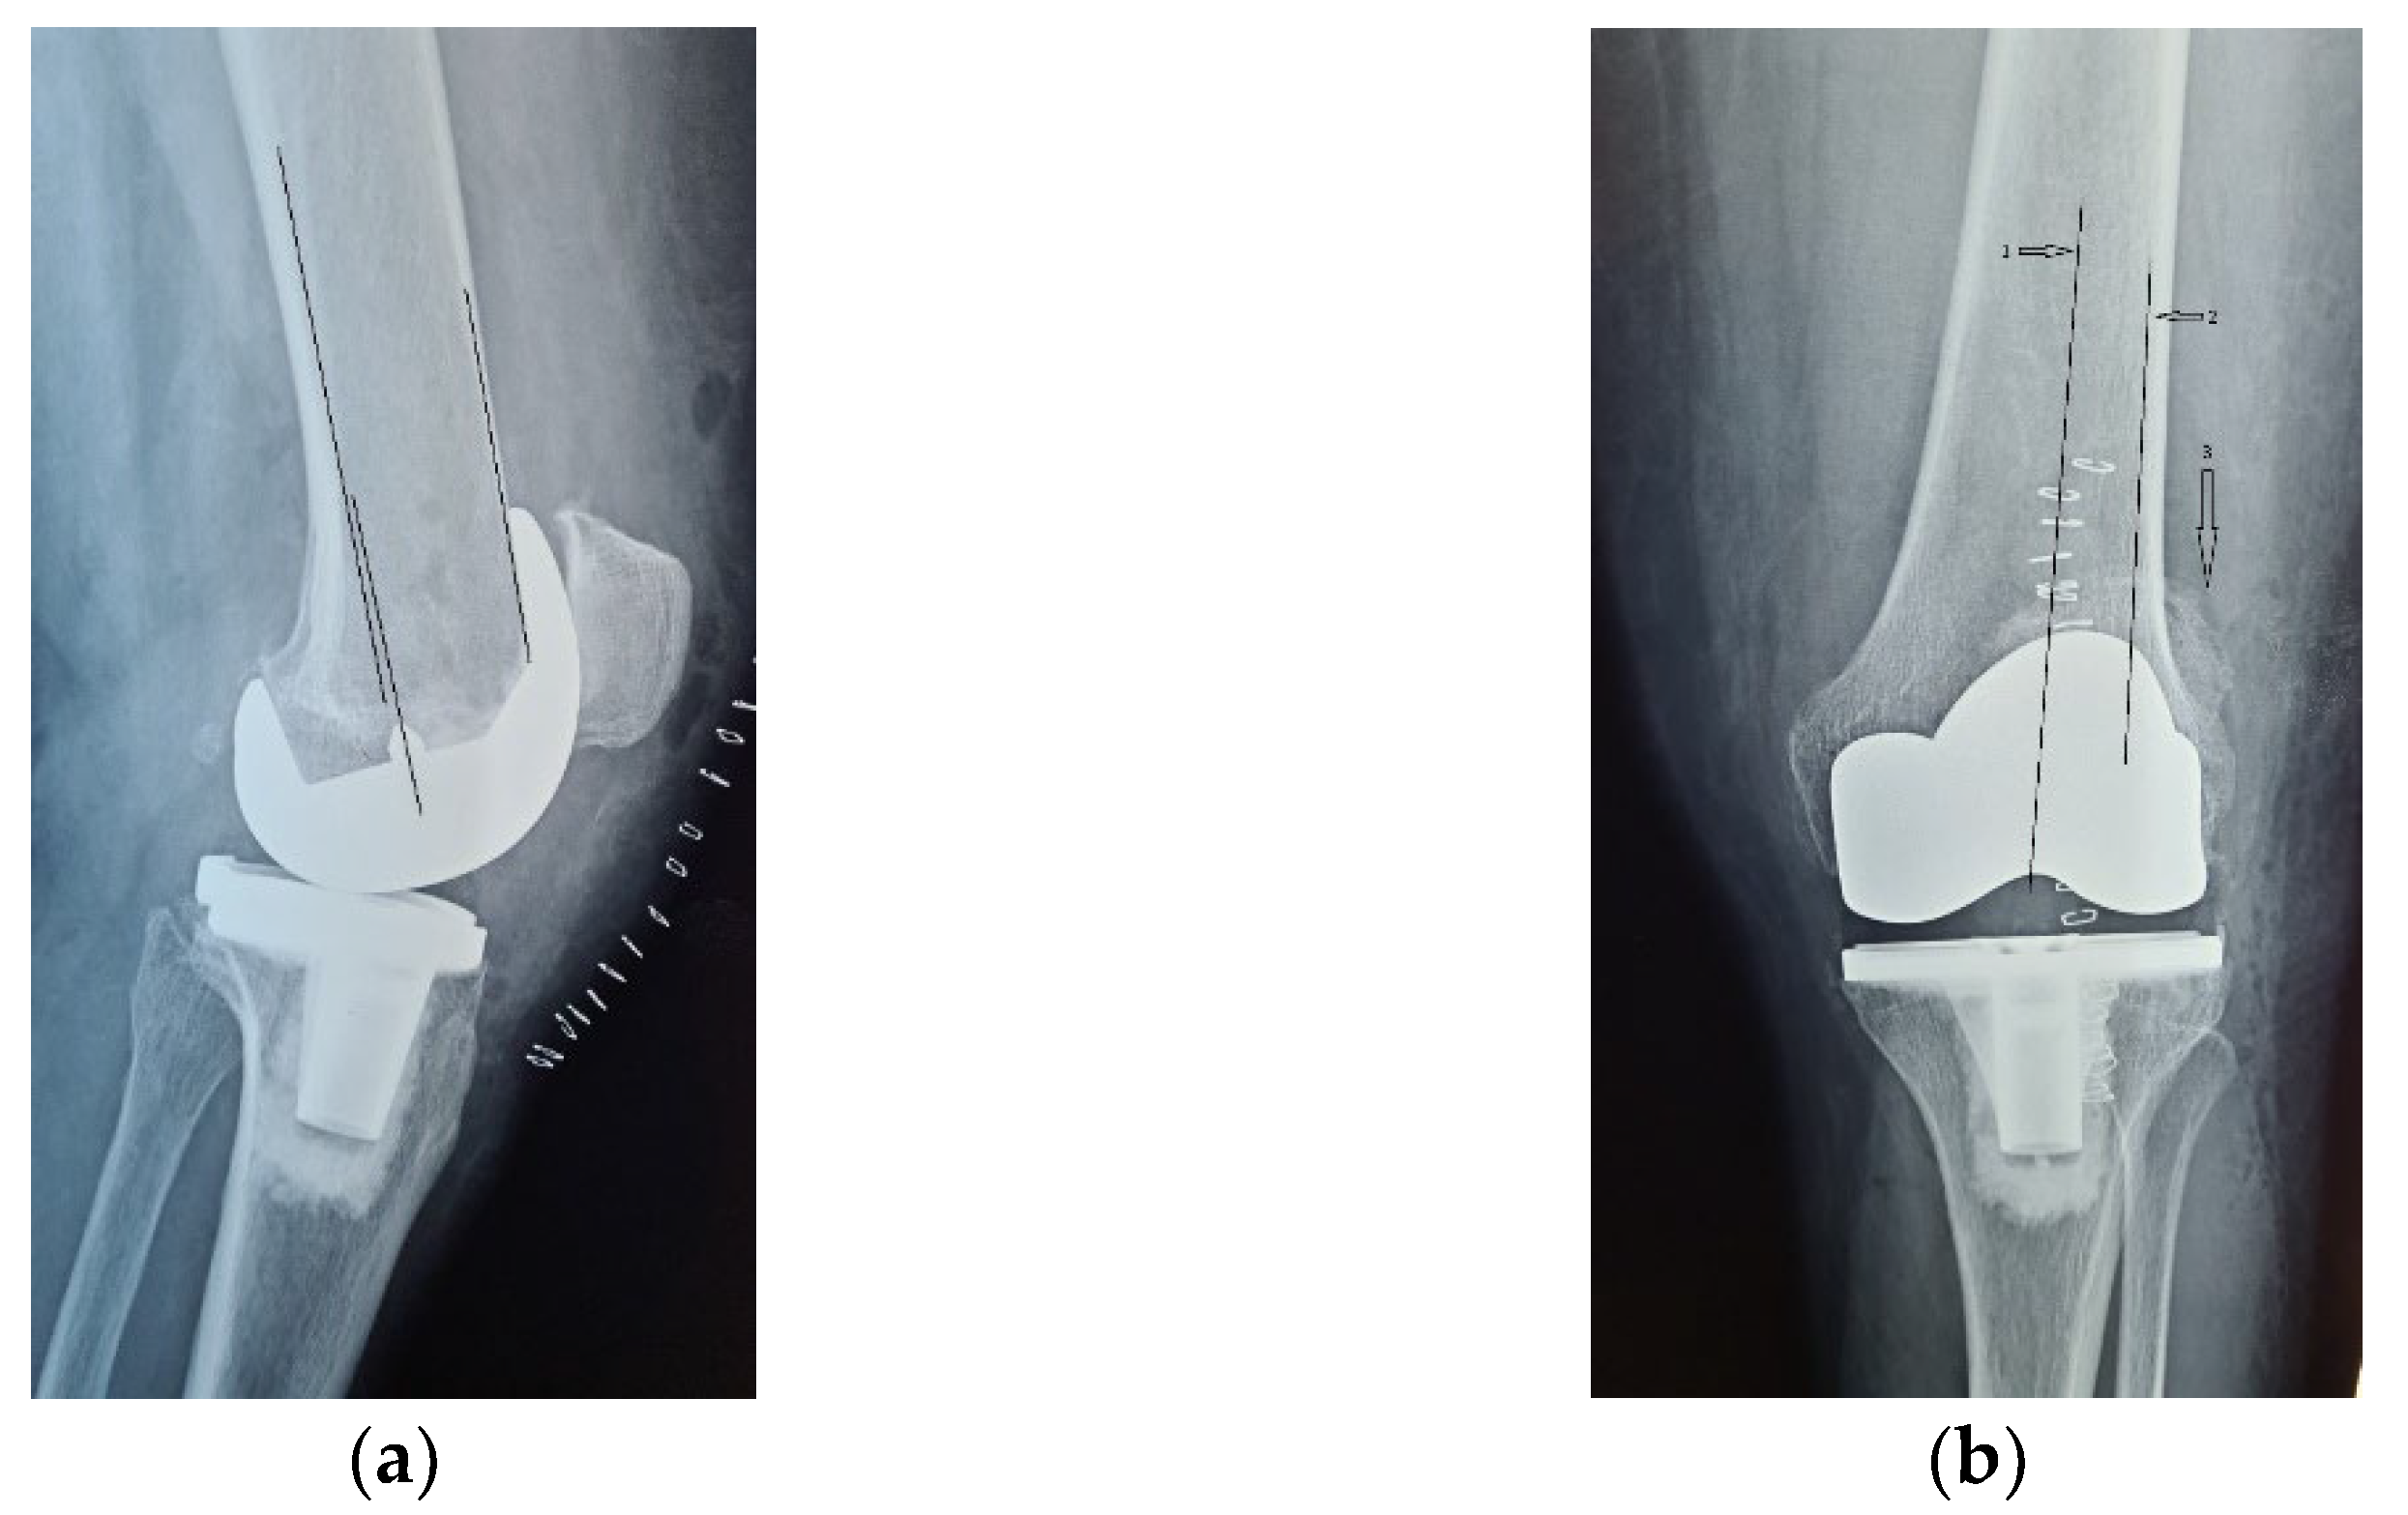

Radiological and clinical follow-up were performed at 6 weeks, 3 months and then 12 months after surgery (Figure 7, Figure 8 and Figure 9).

Figure 8.

Radiological imaging at 3 months after surgery. (a) Coronal view, patella is centered to the femoral component (arrow); (b) lateral view.

Figure 9.

12 months after surgery: (a) coronal view, normal centered patella; (b) lateral view, no signs of patellar loosening; (c) axial view, normal centered patella in femoral trochlea.